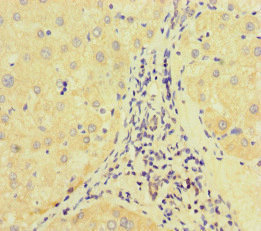

Immunohistochemistry of paraffin-embedded human liver cancer using CSB-PA007340LA01HU at dilution of 1:100